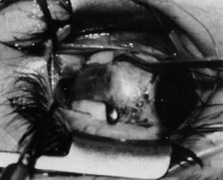

Step 3. Although traction is applied on the superior rectus with the large muscle hook to depress the globe, a Stevens hook held in the other hand is used to expose the superior rectus insertion by reflecting the intermuscular septum, Tenon's capsule, and conjunctiva over the toe of the large hook as shown in Figures 11A (before reflection) and 11B (after reflection).

Fig. 11. A. Traction on the superior rectus muscle with the large muscle hook is applied to depress the globe. B. A Stevens hook held in the other hand is used to expose the superior rectus insertion by reflecting the intermuscular septum, Tenon's capsule, and conjunctiva over the toe of the hook. (Del Monte MA, Archer SM: Atlas of Pediatric Ophthalmology and Strabismus Surgery. New York: Churchill Livingstone, 1993)

Step 4. With the eye maximally depressed with the Green hook beneath the superior rectus, the superior surface of the superior rectus is exposed with two Stevens hooks, as shown in Figure 12. This maneuver exposes the broad, sheetlike white falciform check ligament that fuses to the superior rectus diagonally 8 to 12 mm posterior to its insertion. The ligament is opened centrally at its insertion with blunt Westcott scissors.

Fig. 12. With the eye maximally depressed with the Green hook beneath the superior rectus muscle, the superior surface of the muscle is exposed with two Stevens hooks. The broad, sheet-like white falciform check ligament is exposed. This ligament fuses to the superior rectus muscle diagonally 8 to 12 mm posterior to its insertion. The ligament is opened centrally at its insertion with blunt Westcott scissors. (Del Monte MA, Archer SM: Atlas of Pediatric Ophthalmology and Strabismus Surgery. New York: Churchill Livingstone, 1993)